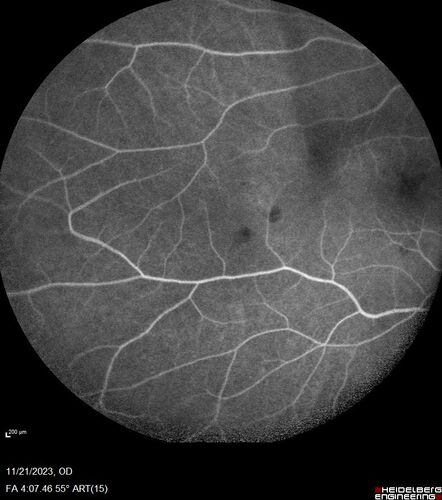

Roth Spot and Endocarditis

70 year old female - flu like symptoms with roth spot who was diagnosed by echo with endocarditis